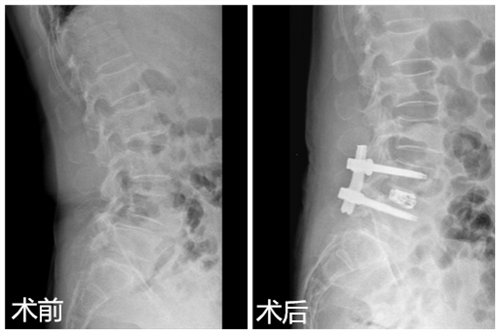

患者刘女士,60岁,腰部疼痛伴双下肢步行受限半年,近1个月出现间歇性跛行。曾到多家医院求治均效果不佳,后慕名来到临床医学院/附属医院疼痛科求医,门诊医师经过检查后诊断为腰椎间盘突出症伴腰椎Ⅱ度滑脱,椎管狭窄,并建议住院治疗。疼痛科医疗团队为患者进行了仔细的体格检查及影像学评估,做好充分的术前准备后,在DSA引导下成功为患者实施椎间孔镜辅助Endo-LIF腰椎融合术。术后第二天,患者腰部疼痛明显缓解,四天后下地活动,受限恢复正常,患者和家属十分满意。

对于腰椎间盘突出症伴腰椎滑脱,传统的治疗方法是开放手术,由于创伤大,风险高,并发症相对较多,很难为患者和家属接受。融合技术作为脊柱治疗中最重要的技术,逐渐发展为从传统开放走向微创。椎间孔镜辅助Endo-LIF腰椎融合术是将内镜技术、融合技术及经皮内固定技术相结合,该技术是经过腰椎后外侧融合,无需像传统开放手术那样对关节突进行切除,无需干扰腰椎后方的肌肉,对患者腰部解剖结构及稳定性破坏极小,在实现手术切口最小化的同时,达到真正意义上的微创。该技术具有切口小、风险低、创伤小、并发症少的优势,很容易被患者和家属所接受,也是以后脊柱外科发展的方向。